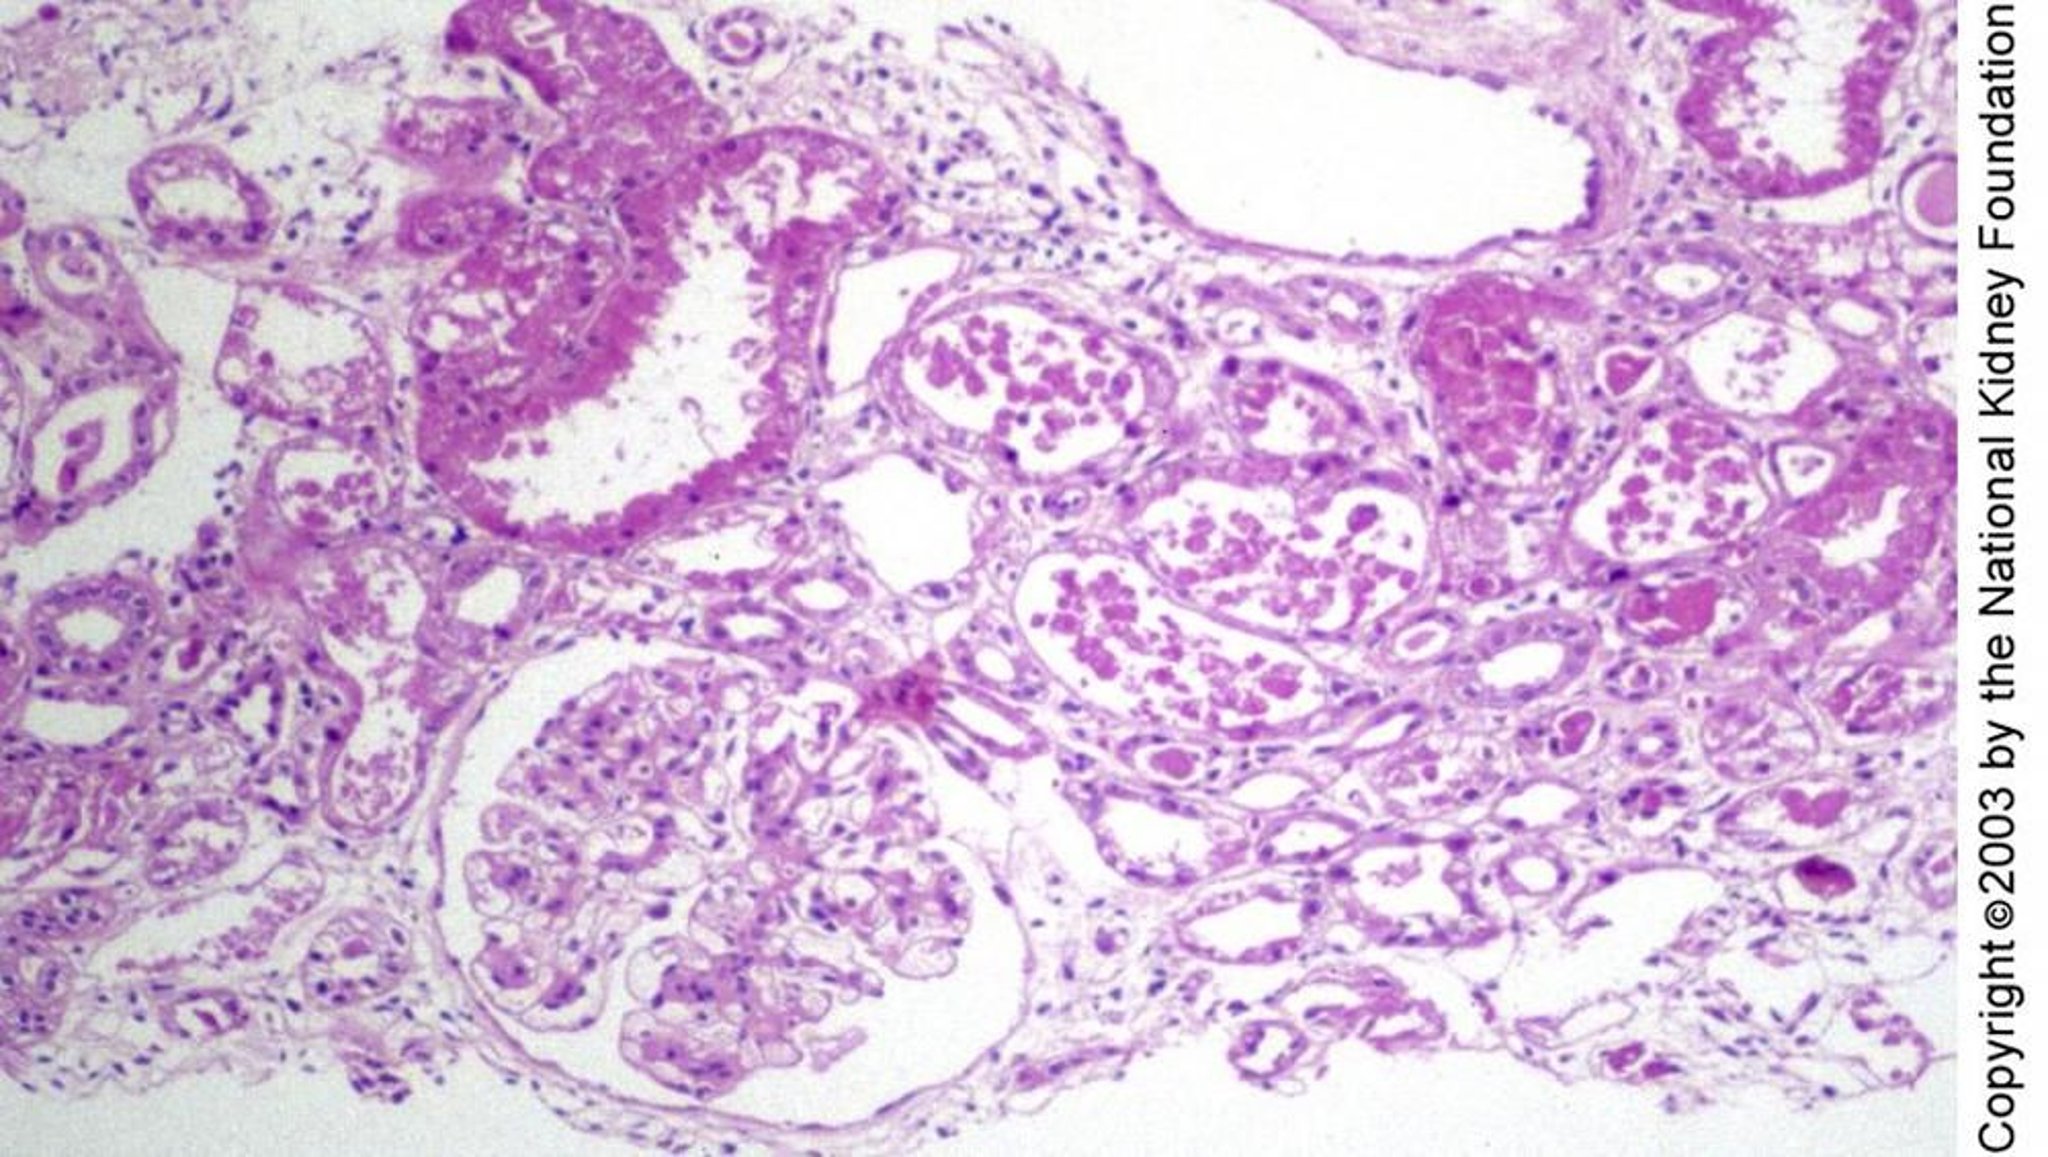

Necrose tubular aguda

A lesão tubular na necrose tubular aguda pode se manifestar histologicamente como regeneração do epitélio tubular plano sem necrose, como visto à direita do glomérulo, bolhas e degeneração celular individual, como no canto superior esquerdo, ou necrose franca, como no meio da imagem (coloração com ácido periódico de Schiff, × 100).

Image provided by Agnes Fogo, MD, and the American Journal of Kidney Diseases' Atlas of Renal Pathology (see www.ajkd.org).